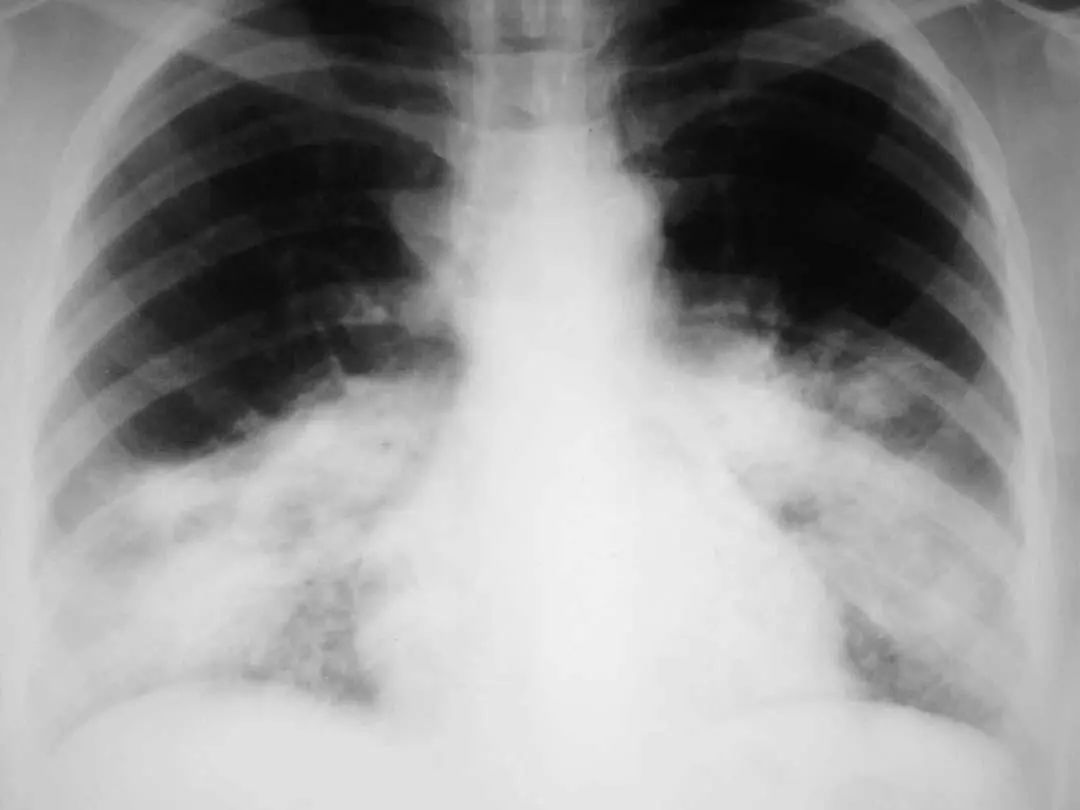

图1.9 49岁肺炎球菌性肺炎患者, 胸部X线片显示左下叶不透明伴胸腔积液。

图1.10 48岁的流感嗜血杆菌性肺炎患者, 胸部X线片显示双侧不透明,主要分布在外周。